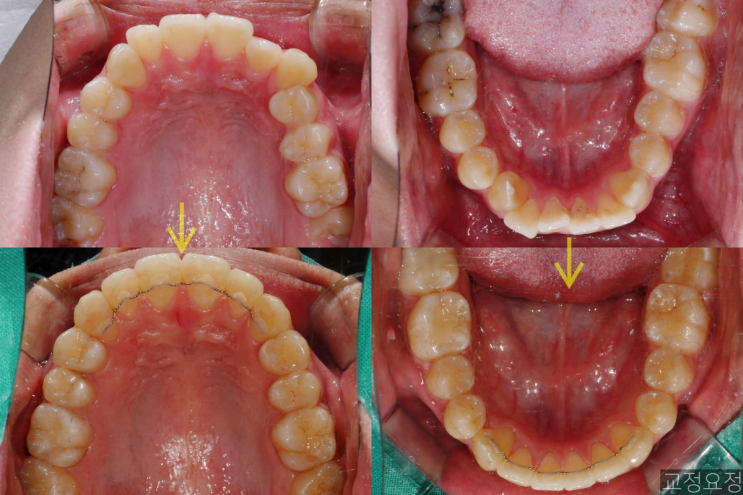

?삐뚤빼뚤한 송곳니 덧니 치아교정 케이스 / 악궁확장 없이 비발치 케이스 - 전후사진, 치료기간, 주의사항

안녕하세요 ! 치과의사 교정요정 입니다. 오늘은 삐뚤빼뚤한 치아를 발치하지 않고 교정한 간단한 케이스 ...